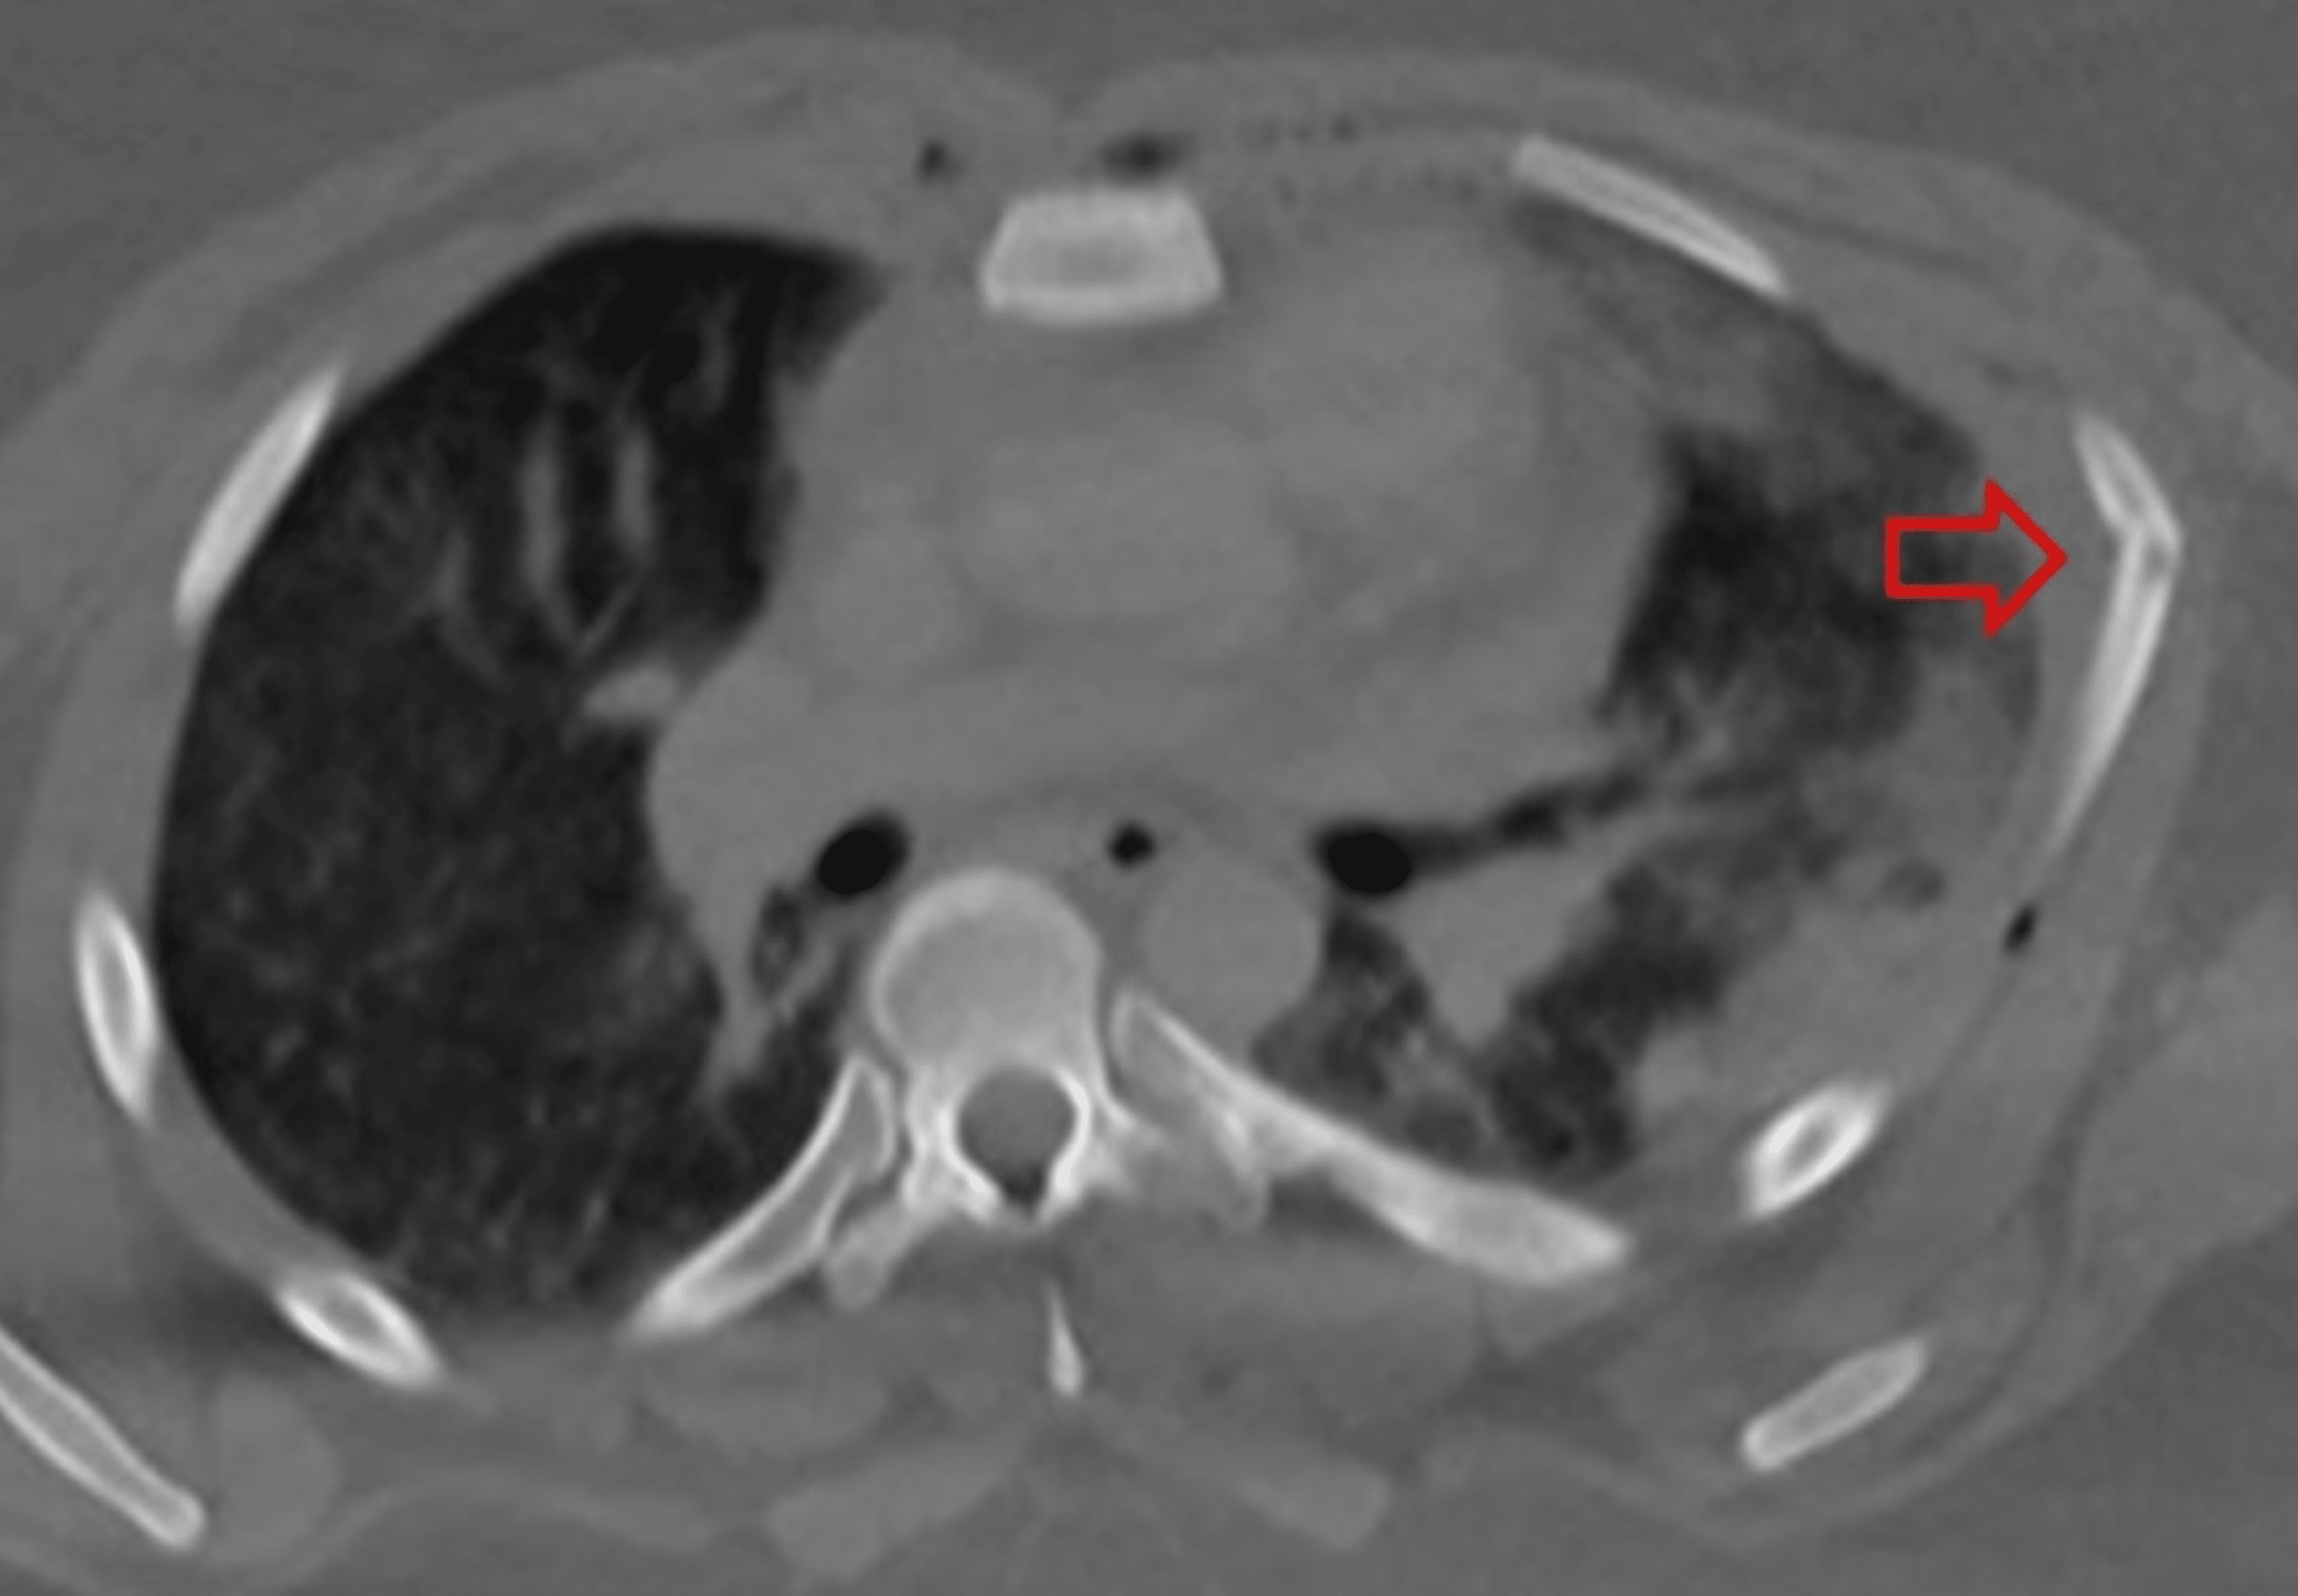

From www.svuhradiology.ie

Sternal fracture Radiology at St. Vincent's University Hospital How To Fix A Fractured Sternum It can take 3 months or longer for the pain to go away. The doctor has checked you carefully,. The most common mechanism of injury is direct blunt trauma to the anterior chest wall. Call 911 anytime you think you may need emergency care. Although some fractures of the rib and/or sternum are treated with pain management and bracing, as. How To Fix A Fractured Sternum.